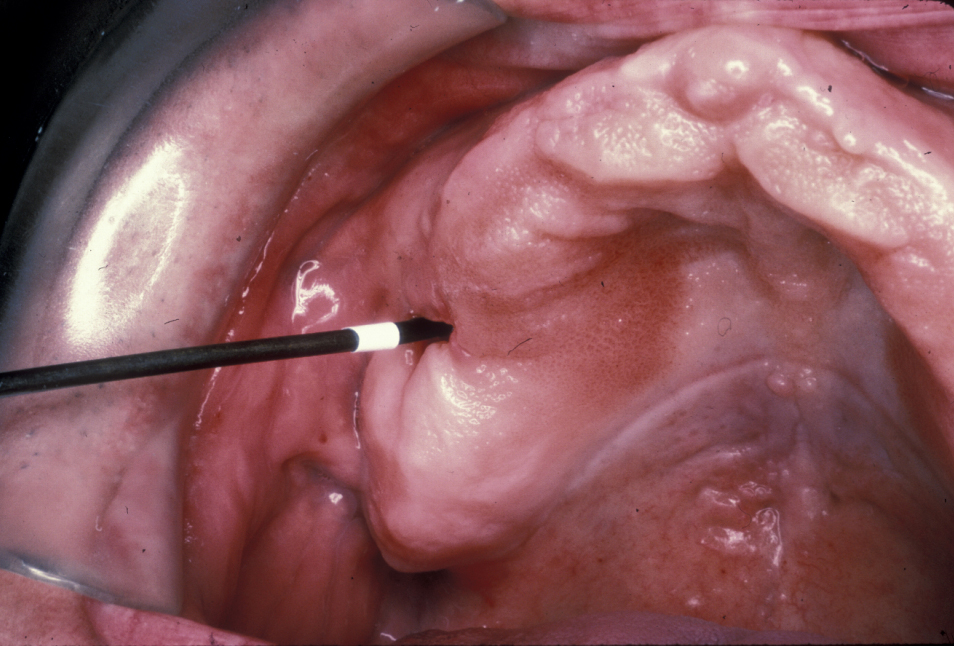

An oroantral fistula (a communication between the oral cavity and the maxillary sinus (antrum) is a common condition. Lining of the antrum may prolapse through such a fistula (Figure 1), or the fistula will have become lined with epithelium (thin, surface-covering tissue) as shown in Figure 2.

Figure 1: Clinical view of antral lining prolapsing through an oroantral communication.